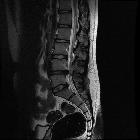

Disc protrusions are a type of disc herniation characterized by protrusion of disc content beyond the normal confines of the intervertebral disc, over a segment less than 25% of the circumference of the disc. The width of the base is wider than the largest diameter of the disc material which projects beyond the normal disc margins. The protrusion must not extend above or below the relevant vertebral endplates .

Additionally, the terms contained (outer annulus fibrosus laminae are intact) and non-contained (all laminae are deficient) are also sometimes used .

A disc extrusion is distinguished from a disc protrusion in that the base of the protruded disc material is narrower than its 'dome'. Furthermore, this material may extend above or below the disc level.